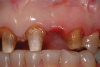

A patient presented with two defective 3-unit fixed partial dentures spanning teeth Nos. 6 through 8 and teeth Nos. 9 through 11 (Figure 7). The defective fixed partial dentures were removed (Figure 8), an impression was made, and traditional provisional fixed partial dentures without ovate pontics were placed. After the impression was sent to the laboratory, the lab technician prepared ovate pontic sites on the stone cast (Figure 9) and fabricated the new definitive bridges. On the day of insertion, the provisional fixed partial dentures were removed (Figure 10), ovate pontic sites were prepared using a teardrop-shaped diamond bur (Figure 11), and the sites were sounded to confirm that there was at least 2 mm from the base of the pontic site to the alveolar bone (Figure 12). The fixed partial dentures were cemented, and the postoperative healing was uneventful (Figure 13).